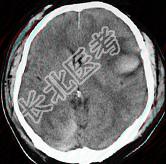

- 单项选择题女,52岁, 有高血压病史,半小时前突感头晕, 剧烈头痛,摔倒在自家楼下, CT检查如图所示,最可能的诊断是 ( )

E、脑出血